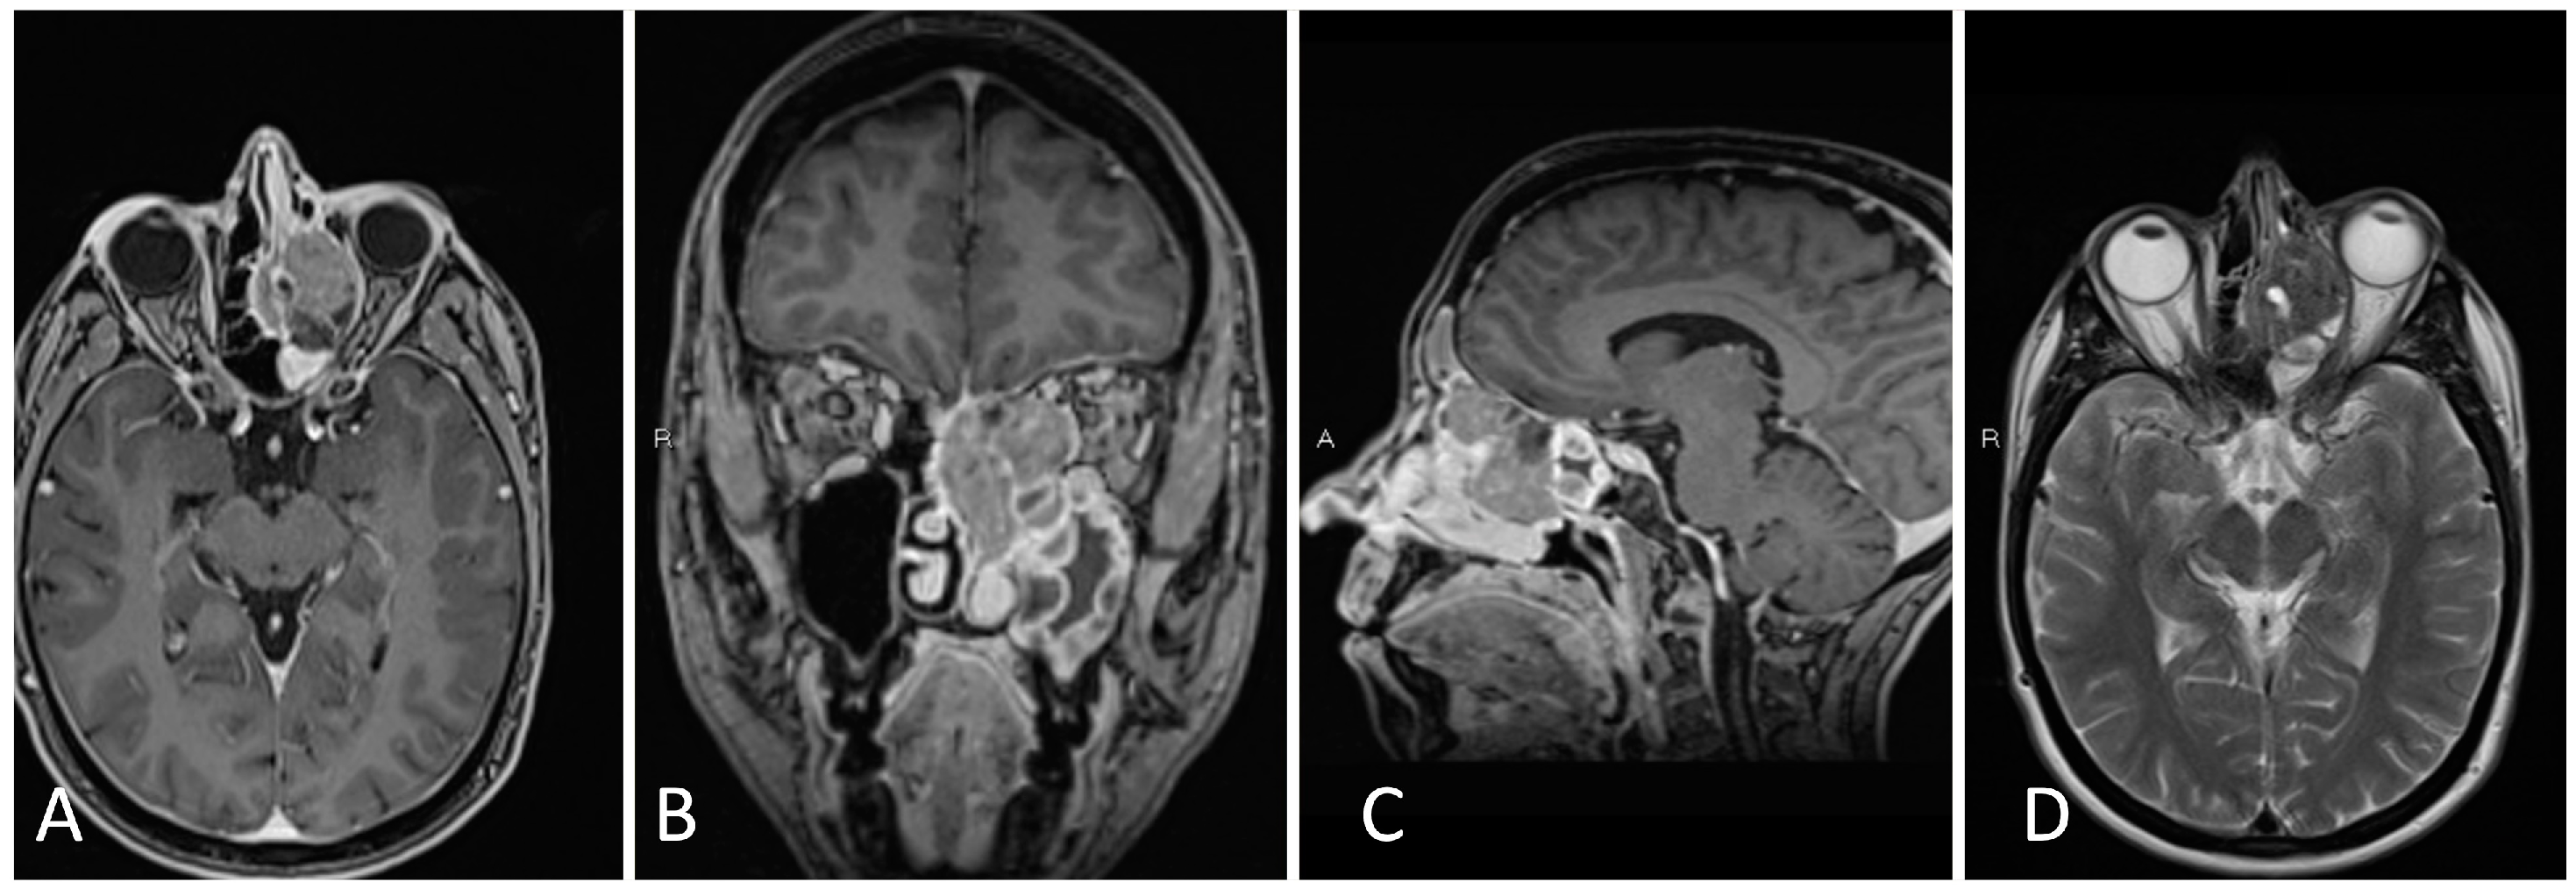

3.4.2. Illustrative Case

3.4.3. Practical Pearls

- Sacrifice of the sphenopalatine artery in the transpterygoid approach precludes an ipsilateral nasoseptal flap.

- Skeletonization of the maxillary nerve leads to the ‘quadrangular space’ and Meckel’s cave.

- Skeletonization of the vidian nerve leads to the lacerum segment of the ICA.

- The contralateral transmaxillary approach may be a useful back up option for lateral petrous pathologies approaching the IAC.